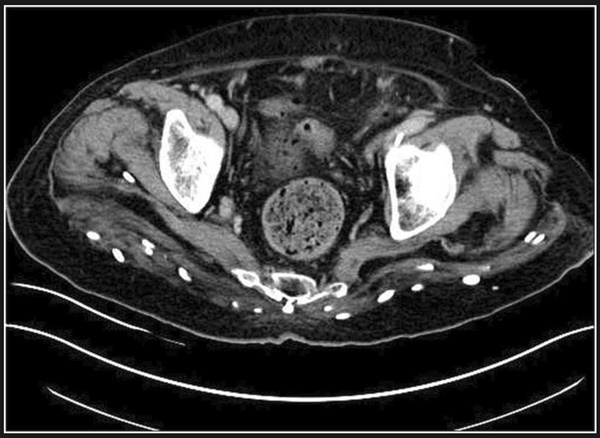

Bác sĩ lập tức chỉ định chụp cộng hưởng từ, chụp cắt lớp vi tính và chụp X-quang cho bệnh nhân. Kết quả, các bác sĩ vô cùng kinh sợ khi phát hiện hàng trăm trứng sán dây nhỏ xíu lúc nhúc trong gần như mọi phần trong cơ thể người bệnh.

Qua hình ảnh chụp chiếu, dễ dàng nhận ra trứng sán dây xuất hiện trong não, cột sống, mông, cổ, ngực và chân cụ ông đã về hưu. Cụ được chẩn đoán mắc bệnh ấu trùng sán lợn. Đây là bệnh nhiễm trùng sán dây, thường là hậu quả của việc ăn thịt lợn bị nhiễm sán.

Hình ảnh trứng sán dây ở cột sống thắt lưng và mông, các chấm trắng cho thấy cụm trứng sán dây trong não của bệnh nhân